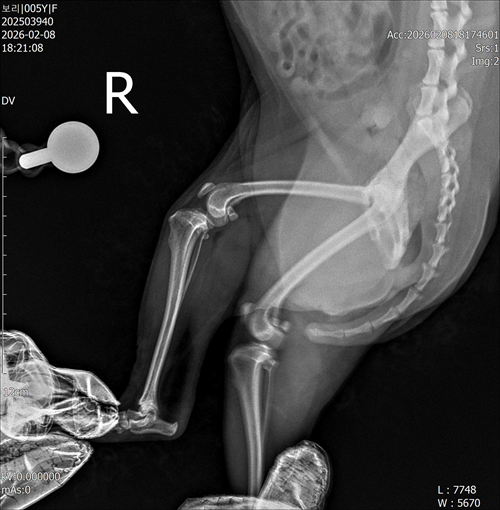

강아지 슬개골탈구 진단 받았습니다 몇군데 병원을 다녀봤는데 진단이 달라 궁금해서 질문 해봅니다 일단 저희 강아지는 오른쪽 다리를 갑자기 들고 다니고 절어 병원을 방문하게 되었고요 왼쪽은 증상이 없지만 오른쪽만 있는 상태였습니다 첫번째랑 두번째 병원에서는 슬개골 탈구 진행중이고 왼쪽이 3기 오른쪽이 2기 정도라고 했습니다 하지만 왼쪽은 아예 빠져있어 증상도 없고 아파하지도 않는다고 했고 오른쪽은 빠졌다 안빠졌다 해서 증상이 있다고 했고 십자인대가 파열된 걸론 보이지 않는다고 했습니다 그래서 양쪽 슬개골탈구 수술만 진행하면 된다고 했고요 근데 세번째 병원에서는 둘다 왼쪽이 좀 더 심한 슬개골 탈구 3기 정도라고 했고 오른쪽만 십자인대 부분파열이 보인다고 했습니다 그래서 십자인대 파열이 아닌 왼쪽은 굳이 수술할 필요가 없고 나중에 십자인대 파열이 오거나 증상이 나타나면 그때 수술하면 된다고 했습니다 그래서 오른쪽 슬개골탈구 수술과 tplo를 하는 방식으로 수술을 한다고 했습니다 여기서 궁금한점은